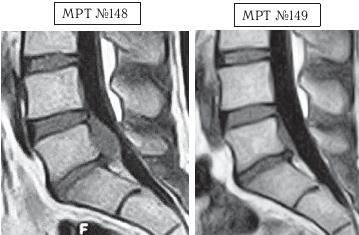

На МРТ №146 в поясничном отделе позвоночника наблюдается секвестрированная грыжа межпозвонкового диска в сегменте LIV-LV с разрывом задней продольной связки. На МРТ № 147 наблюдается результат после одного курса лечения методом вертеброревитологии. Этот случай особо запомнился своей сложностью, а также большим желанием данного человека восстановить утраченное здоровье. ![]() На МРТ № 148 наблюдается состояние поясничного отдела позвоночника после хирургических операций: рецидив грыжи межпозвонкового диска в сегменте LV-SI, осложнённой массивным секвестром с краниальной миграцией. Размер грыжи до 15 мм дорсально (кзади) и до 34 мм — краниально (вверх). На МРТ № 149 наблюдается состояние поясничного отдела позвоночника после одного курса лечения методом вертеброревитологии. Вот ещё один любопытный результат из этого раздела документальной медицинской информации, который заслуживает внимания.